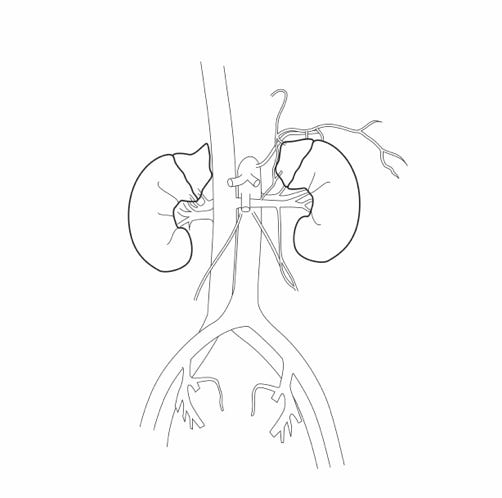

Über die Gefäße, Nerven und Faszien gelingt es, dem Menschen zu einer guten Regeneration zu verhelfen. Dies ist die Grundlage des Behandlungsprinzips Stärkung der Homöostase.